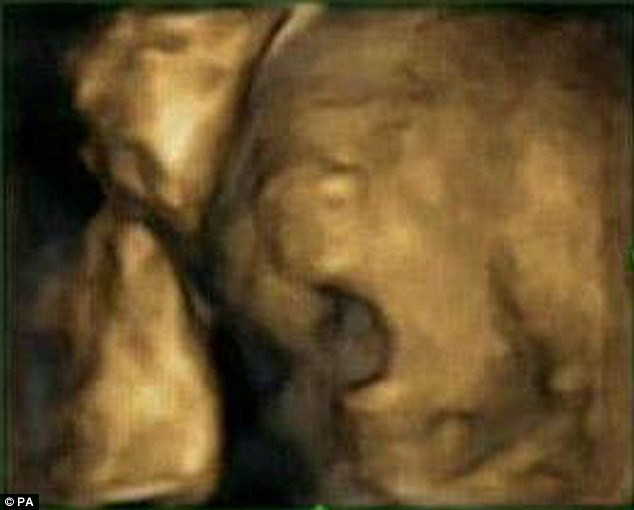

Anne karnındaki bebeğin esneme anları - Resim: 2

Araştırmayı yürüten ekibin başındaki Nadja Reissland, “Anne karnındaki bebeğin esnemesinin fonksiyonunu ve önemini halen bilmiyoruz. Ancak elde ettiğimiz veriler, esnemenin cenin gelişimi ve bebeğin sağlık belirtileri ile bağlantılı olabileceğini gösteriyor. Rahimdeki bebeğin esneme sıklığı, erken gebelikte beynin olgunlaşması ile ilgili olabilir” açıklamasını yaptı.